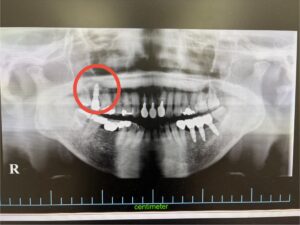

レントゲン検査などで診査・診断を行ったところ、歯根破折が確認されました。

術前写真